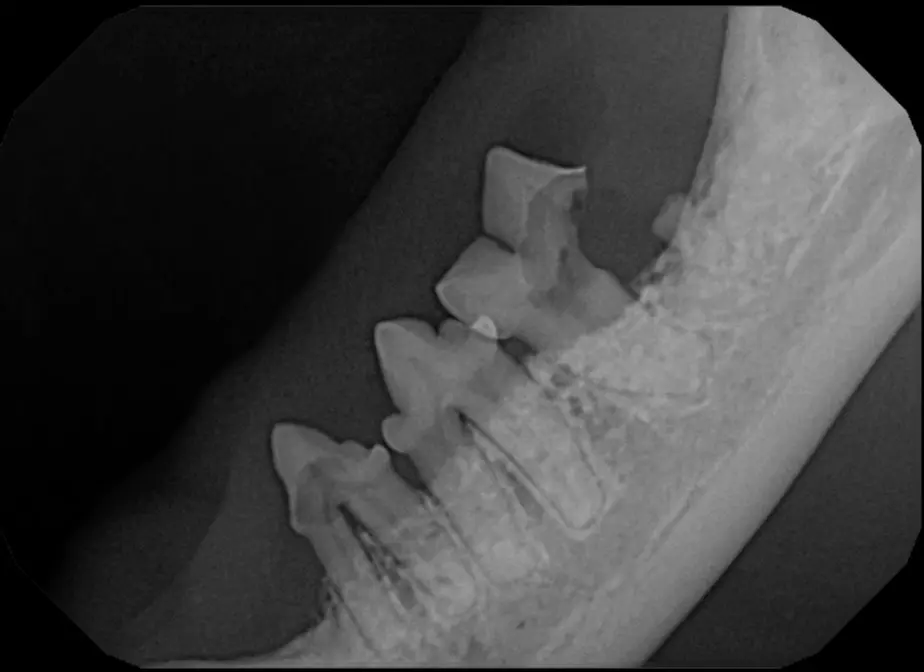

Periodontal disease is extremely common in dogs and cats. Over 80% of dogs and cats over two years of age have some degree of periodontal disease. Periodontal disease is best prevented by yearly professional dental cleanings starting at two years of age and at home brushing at least three times weekly. Brushing should begin at a very early age to allow your new pet to get used to regular brushing. In severe cases of infection or periodontal disease, the teeth may need to be surgically extracted. Extractions should always involve x-rays of the tooth first, as many teeth have multiple roots or may be diseased below where the eye can see. Extracting larger teeth in animals requires oral surgery, equivalent to removing wisdom teeth in people. It is vital that all of the tooth and roots be removed for the periodontal infection to resolve. In cases of important teeth with mild to moderate periodontal disease, multiple periodontal treatments can be offered to help save these teeth.